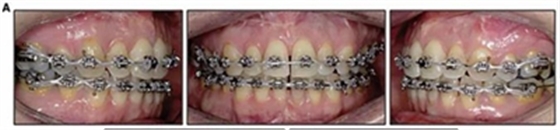

患者側(cè)貌改善,下唇唇肌緊張消失,上下唇可自然閉合。磨牙及尖牙關(guān)系糾正至I類(lèi),覆合覆蓋正常。上下頜弓型糾正至卵圓形,牙弓寬度增加。頭影測(cè)量分析示SNA角81.8°,ANB角3°。頭影測(cè)量重疊圖示下頜骨向后旋轉(zhuǎn),垂直面高度略有增加。

19個(gè)月后復(fù)查,情況穩(wěn)定,牙弓寬度穩(wěn)定。